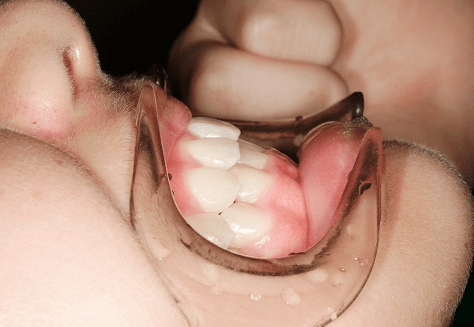

M.M

治療前

治療後

主訴

嚙み合わせが悪い。八重歯が気になる。

診断

叢生・反対咬合

年齢/性別

10代/女性

抜歯部位

非抜歯

使用装置

インビザラインファースト→インビザラインフェーズⅡ(部分的にワイヤーにて処置)

保定装置

上下ビベラリテーナー

料金

初回資料採得・・・・・・・30,000円

診断料・・・・・・・・・・0円

動的治療終了時資料採得・・5,500円 -

基本料金

円ファースト時:450,000円

フェーズⅡ時:240,000円 -

診察料金

ファースト時:0円×16回

フェーズⅡ時:5,500円×9回

ワイヤー併用時:8,800円×2回 -

治療期間

2年7カ月